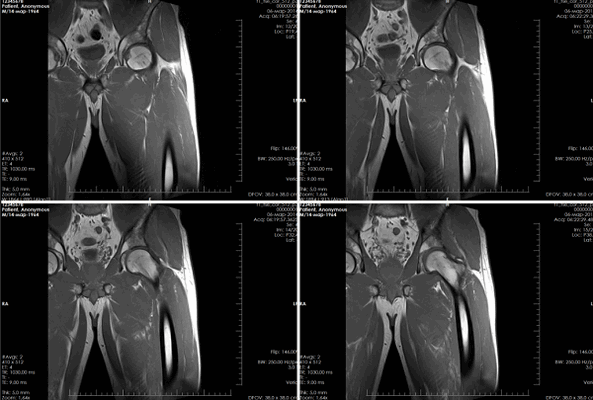

Рисунки 1,2. МР-картина артроза тазобедренных суставов с наличием отека костного мозга дистрофического характера в верхне-наружных отделах вертлужной впадины справа

Рисунок 3. МРТ тазобедренных суставов в косо-аксиальной плоскости.

Суставной хрящ головки бедренной кости и правой вертлужной впадины с обеих сторон однородной структуры, неравномерной толщины, целость его не нарушена. Головка бедренной кости сферичная, шейка не укорочена, не утолщена.